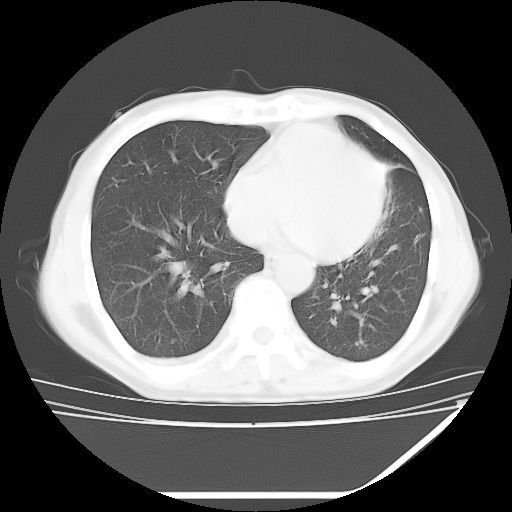

男,59岁,“结核性胸膜炎”30余年,胸部经常疼痛,多次x检查提示“肺部”炎症。腹部疼痛5日,b超提示:“肝内短管结石,余显示不清,建议进一步检查。”

两肺结核并右侧胸腔积液;脾脏、腹腔及腹膜后淋巴结结核[陈旧性];肝内胆管结石

胸部腹部都是结核(双肺。纵隔淋巴结,肝脏,脾脏,肠系膜)

两肺结核并右侧胸腔积液;脾脏、腹腔及腹膜后淋巴结结核[陈旧性];肝内胆管结石。直肠息肉?